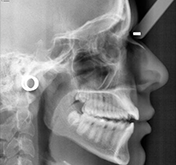

Determining the exact cause of the problem is possible only for a trained orthodontist using patient x-rays, plaster models and photographs. Using these he will analyze the case and will pinpoint the problem and offer a treatment plan to the patient.

Orhodontic Model and X-rays